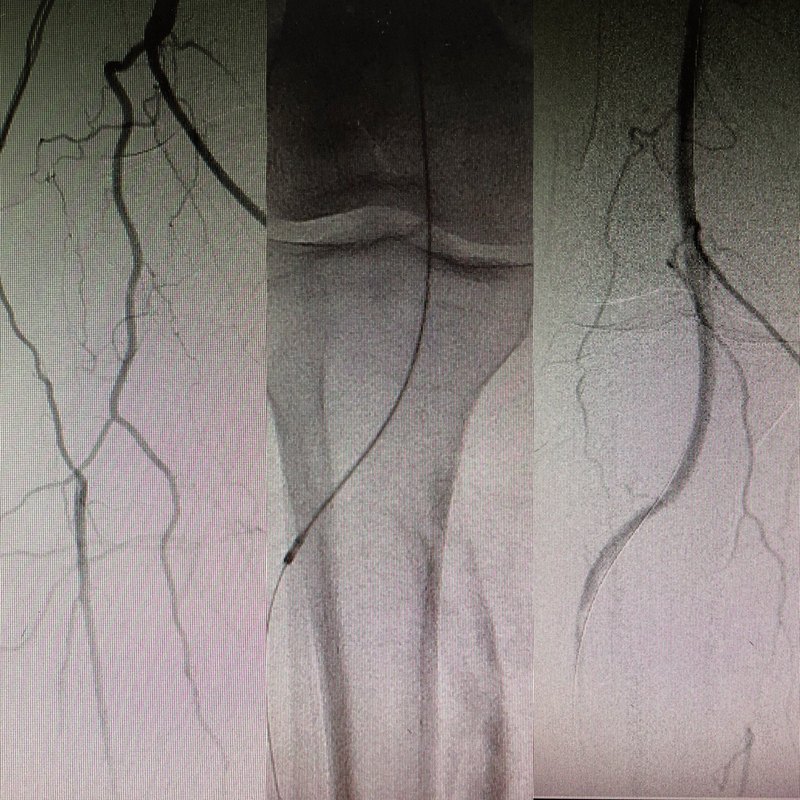

陳阿姨4個(gè)月前出現(xiàn)走路后突然腿痛,自述感覺腳熱一下,就出現(xiàn)走路走的會(huì)疼,也沒什么在意,就沒去管它,過了十幾天另一只腳也是出現(xiàn)這樣情況,就趕緊到醫(yī)院看,檢查后發(fā)現(xiàn)是雙下肢的動(dòng)脈堵了,需要開通血管才能緩解癥狀,不然就只能走100米就腳痛了,經(jīng)過介入微創(chuàng)治療,開通血管,正常行走了